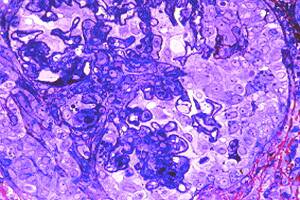

Fig# 13. GNPP III. CA3, CC1 (OMS IVB,C?): GNPP con GNMP, y trombos hyalinos y fibrosis temprana. MOAR 400X.